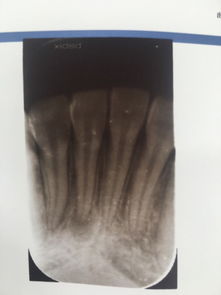

導致牙根發(fā)炎的因素有很多,出現(xiàn)的時候要及時進行治療。那么,牙根發(fā)炎怎么辦?

牙根炎癥的存在,會反復腫痛,影響牙齒的咀嚼功能,嚴重會造成牙的喪失。這樣不僅會影響消化功能,而且在童年時期會影響面部的發(fā)育。此外,有的牙根炎癥進一步發(fā)展會導致全身其它器官的病變。

5、如果牙根發(fā)炎的比較厲害引起牙髓炎或根尖周炎,咨詢醫(yī)生是否需要做根管治療術。